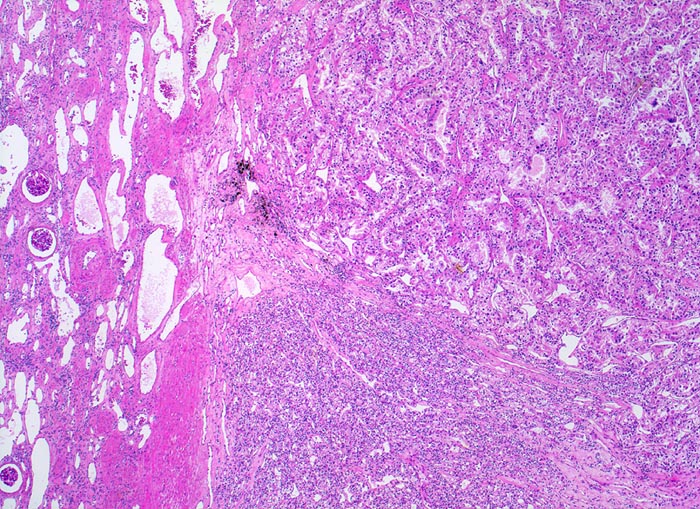

Die Grenze zwischen Karzinom und Nierenparenchym ist scharf und enthält zahlreiche erweiterte Gefässe. Das Karzinom bildet im oberen Anteil drüsige Strukturen, der untere Anteil erscheint solide.

Hellzellige Nierenzellkarzinome zeigen ein expansiv verdrängendes Wachstum an der Tumorinvasionsfront.